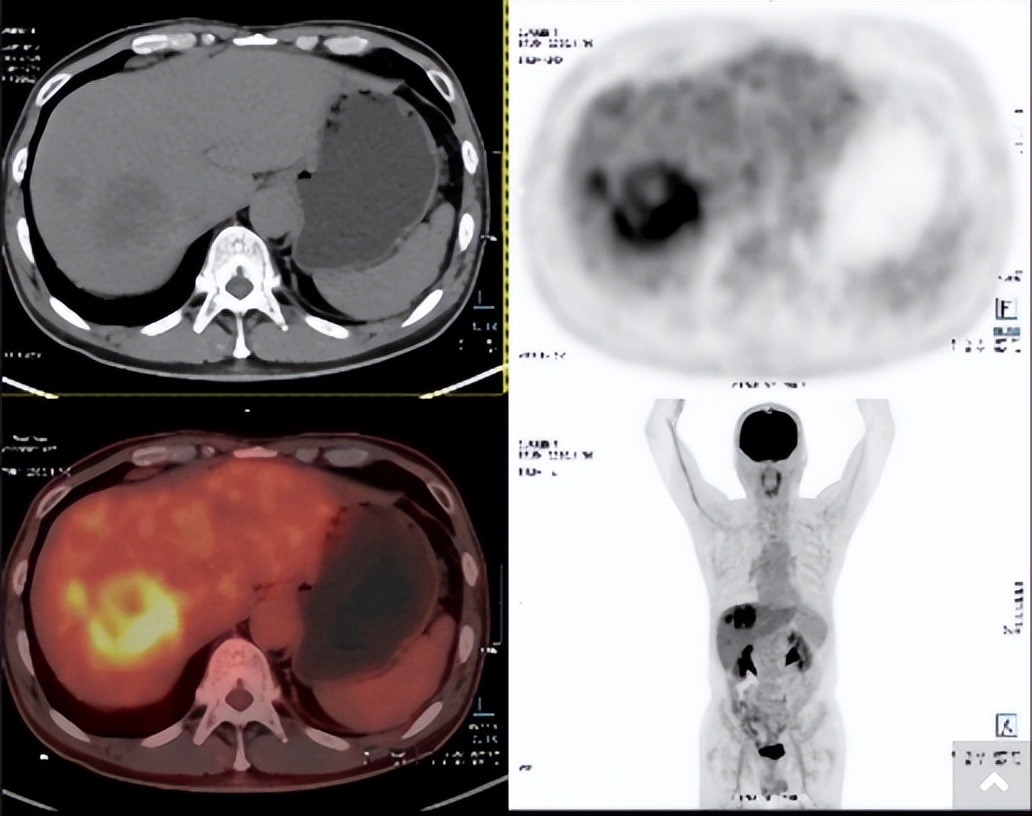

遗憾的是,患者术后13个月复查时发现疾病复发转移。2020年11月10日,核磁共振及PET-CT检查均显示肝脏右叶存在58×46 mm病灶,其旁出现较小转移灶,且合并肝脏右肝静脉受侵,未发现其他部位明确转移灶。

△2020年11月10日MRI

△2020年11月10日PET-CT